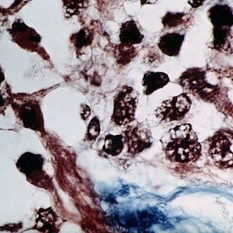

Phycomycoses. Basophilic fungi are seen in the walls of both thrombosed orbital blood vessels (H&E x54).

Condition/keywords: basophilic, phycomycosis, thrombosed hemorrhoid